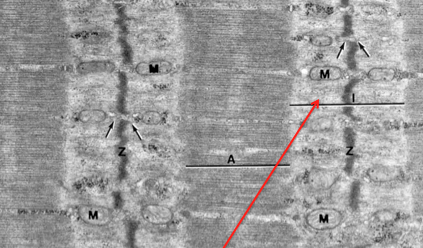

z band

M band